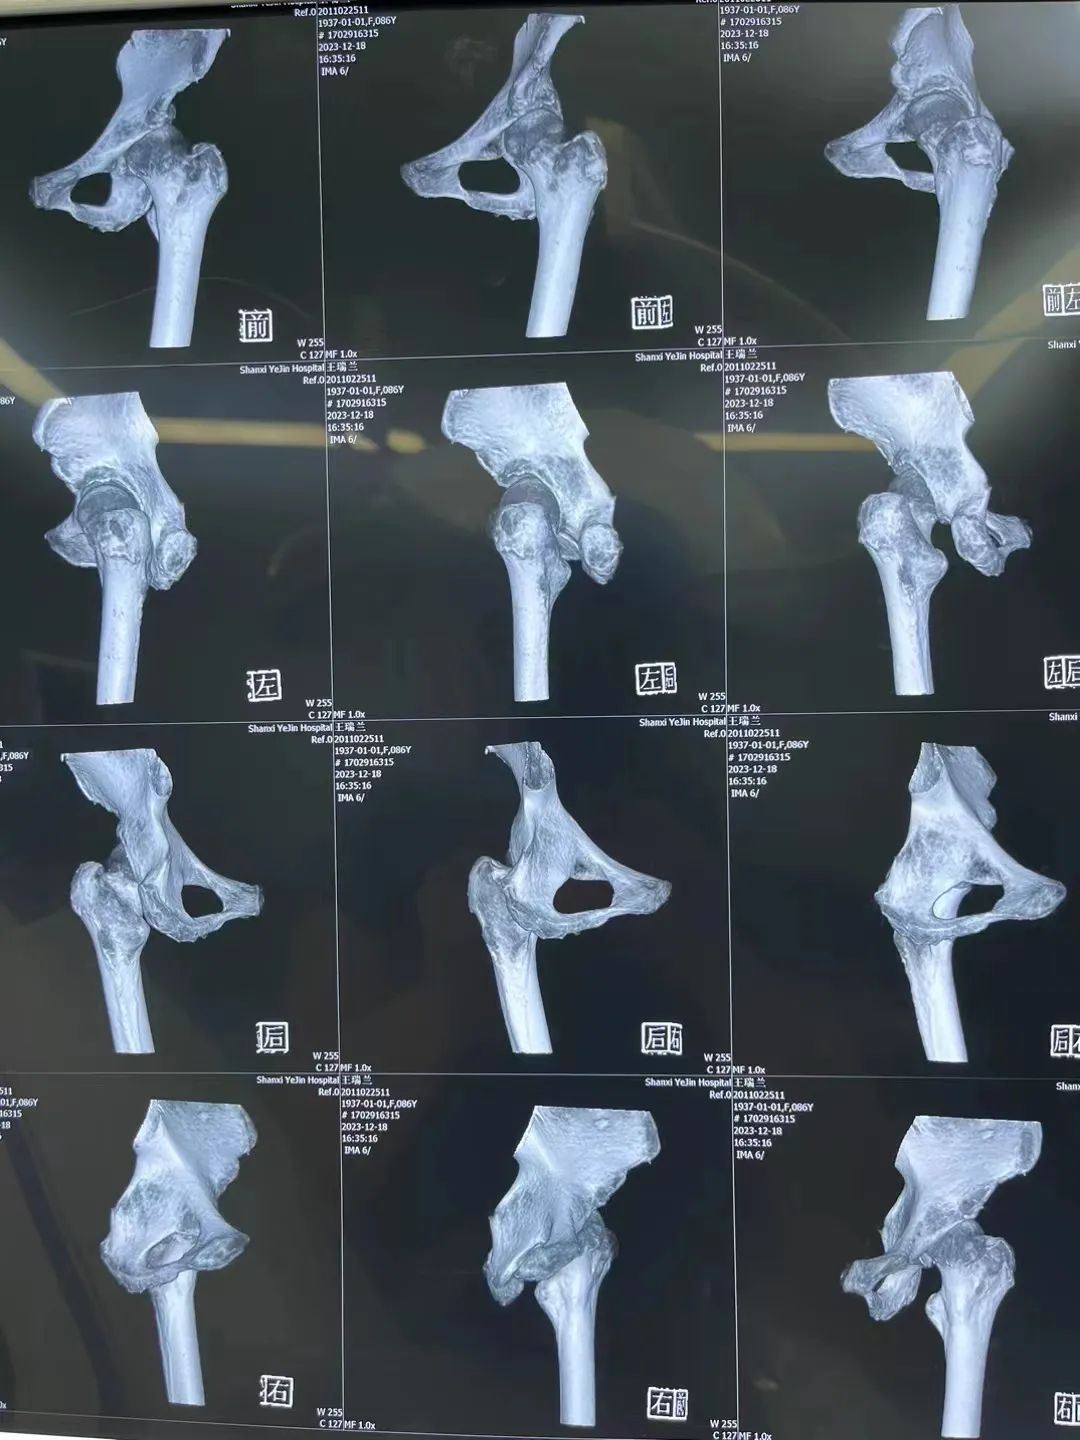

86岁的王奶奶(化名),在家中不慎跌倒,左髋部着地,导致左股骨颈骨折。因有严重的心脏病还装有心脏起搏器,合并多种基础病,辗转多家医院未能手术,经朋友介绍王奶奶在家属的陪伴下来到陕西冶金医院骨科就诊。

▲ 图:王奶奶的X光片